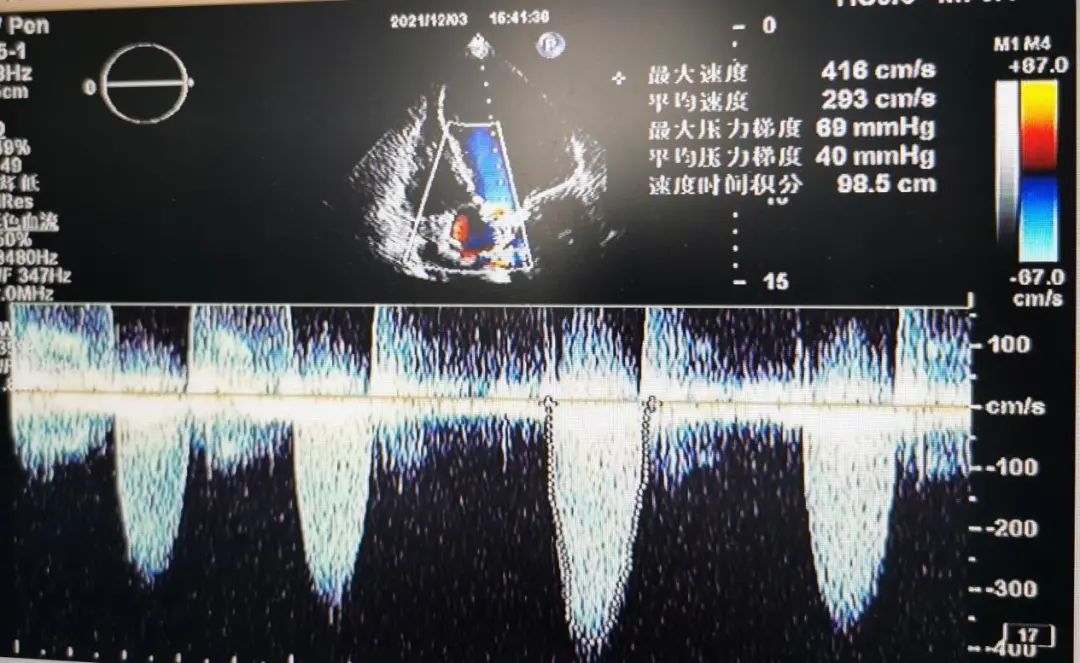

76岁男性,反复胸闷,气促1余年,加重3个月,重度主动脉瓣狭窄(EF42%,4.62m/s)。

术前超声检查: